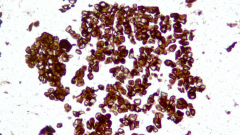

| Description | CLDN18.2是Claudin蛋白質(zhì)家族的一員,位于細胞膜表面,Claudin18.2(CLDN18.2)表達具有特異性。其作為Claudins蛋白的一個(gè)亞型,在正常組織中僅表達于分化的胃黏膜上皮細胞。在胃癌、食管癌和胰腺癌等多種腫瘤中表達,并且不僅限于原發(fā)病灶,在轉移灶中也有表達。目前臨床研究中使用的檢測方法均為免疫組化。 |

| 示例 | ![]() |

| IHC染色結果 | |